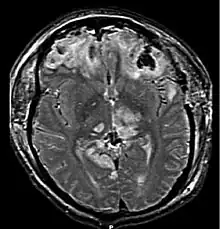

MRI showing injury due to brain herniation

MRI showing damage due to herniation. This patient was left with residual disabilities including those involving movement and speech.[16]

Treatment involves removal of the etiologic mass and decompressive craniectomy. Brain herniation can cause severe disability or death. In fact, when herniation is visible on a CT scan, the prognosis for a meaningful recovery of neurological function is poor.[2] The patient may become paralyzed on the same side as the lesion causing the pressure, or damage to parts of the brain caused by herniation may cause paralysis on the side opposite the lesion.[11] Damage to the midbrain, which contains the reticular activating network which regulates consciousness, will result in coma.[11] Damage to the cardio-respiratory centers in the medulla oblongata will cause respiratory arrest and (secondarily) cardiac arrest.[11] Investigation is underway regarding the use of neuroprotective agents during the prolonged post-traumatic period of brain hypersensitivity associated with the syndrome.[17]